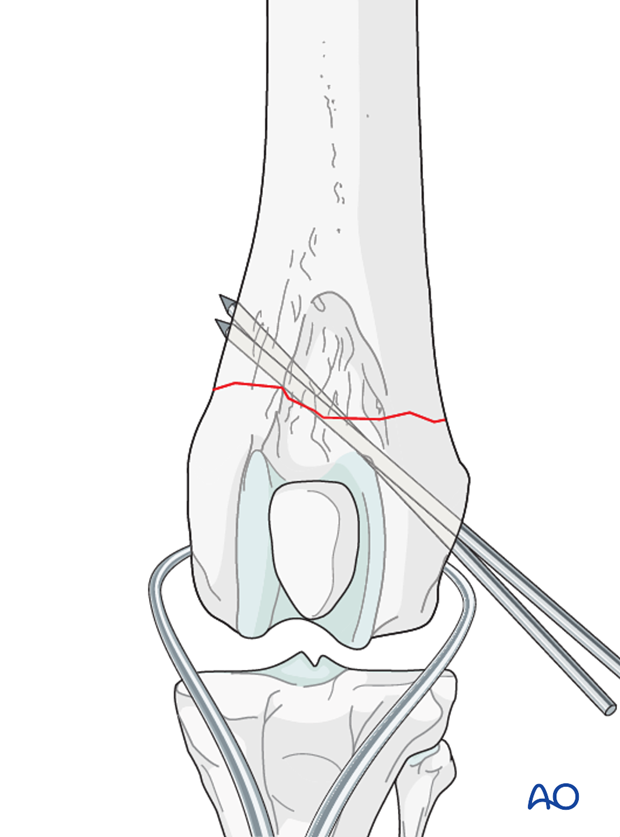

The fracture is reduced with pointed reduction forceps. Anatomic reduction is desired in all cases.

Preliminary stabilization can be achieved with reduction forceps or K-wires.

The K wires can be left in place for additional stabilization with the bone plate.